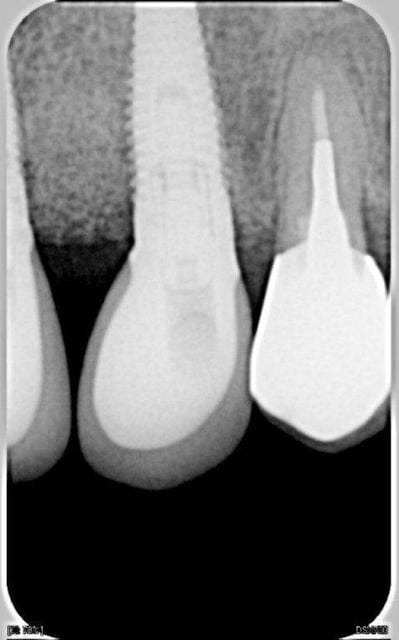

voici la radio de l'implant douloureux au serrage ( le nobel replace) et une radio d'un euroteknica sur lequel j'ai eu le meme probleme : celui de droite ( diam 4.8), pas de pb avec le gauche.

est-ce qu'ils vous paraissent " fibro-integrés"?